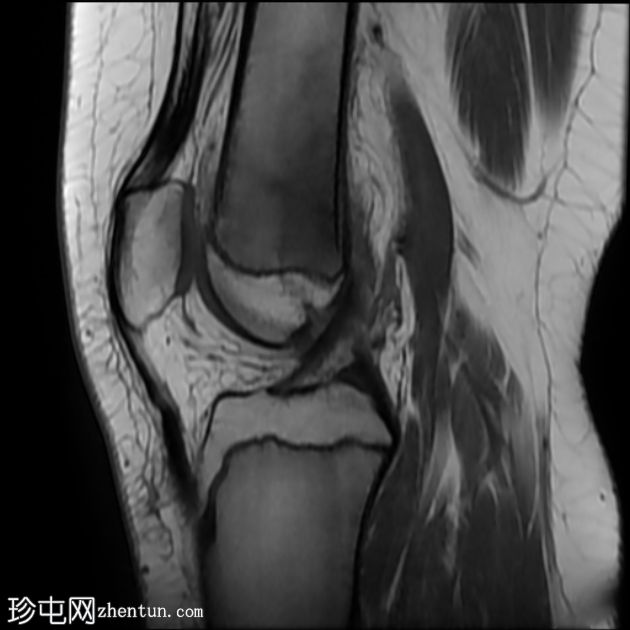

3.jpeg

矢状位

STIR

股骨远端干骺端横向应力骨折线,在所有脉冲序列(T1、T2和STIR)上均呈低信号。其周围有骨髓水肿样信号。邻近骨膜软组织呈水肿样信号。

最初针对胫骨应力性损伤提出的MRI分级方案:

1级:骨膜水肿,无骨髓改变

2级:脂肪饱和T2加权像上可见骨髓水肿样信号

3级:T1加权像上也清晰可见骨髓水肿样信号

4级:T1和/或T2加权像上可见骨折线